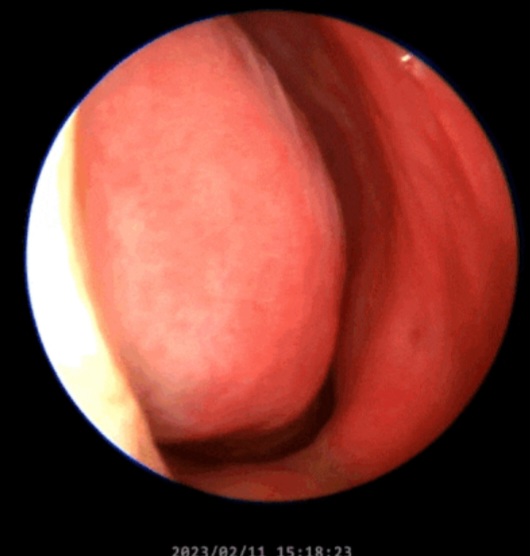

진정한 비염 관리는 내 코 점막이 어떤 상태인지 정확히 파악하는 것에서 시작됩니다. 현재 본인의 점막이 선홍색을 띠고 있는지, 아니면 하얗게 빈혈 상태인지, 혹은 지나치게 부어있는지 전문가의 진단을 통해 확인해야 합니다. 코밤 비강확장밴드는 그 진단 이후에 아주 보조적으로만 사용되어야 할 도구일 뿐입니다.